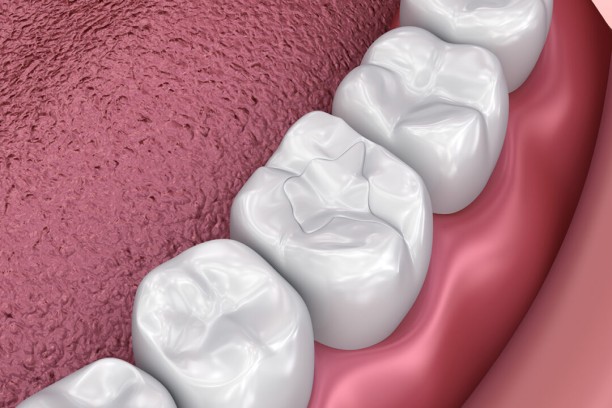

Tooth-Coloured Fillings

Natural looking fillings that blend with your teeth while treating decay.

Dental Fillings

Restores decayed teeth and brings back natural shape and function